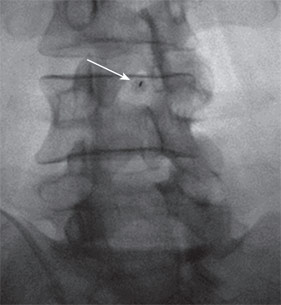

تصویر فلوروسکوپی سوزن در فضای ساب آراکنوئید: